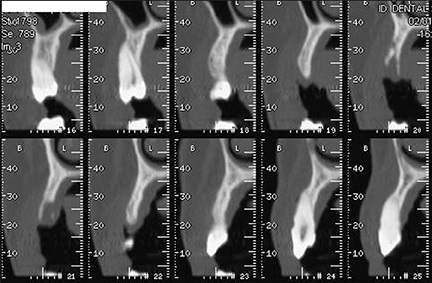

First- and second-level radiographic examinations (panoramic X-ray and CBCT) revealed a marked horizontal atrophy with a moderate vertical component (Figs. 2–3).

Fig. 2: CBCT cross sections

Fig. 3: CBCT axial view